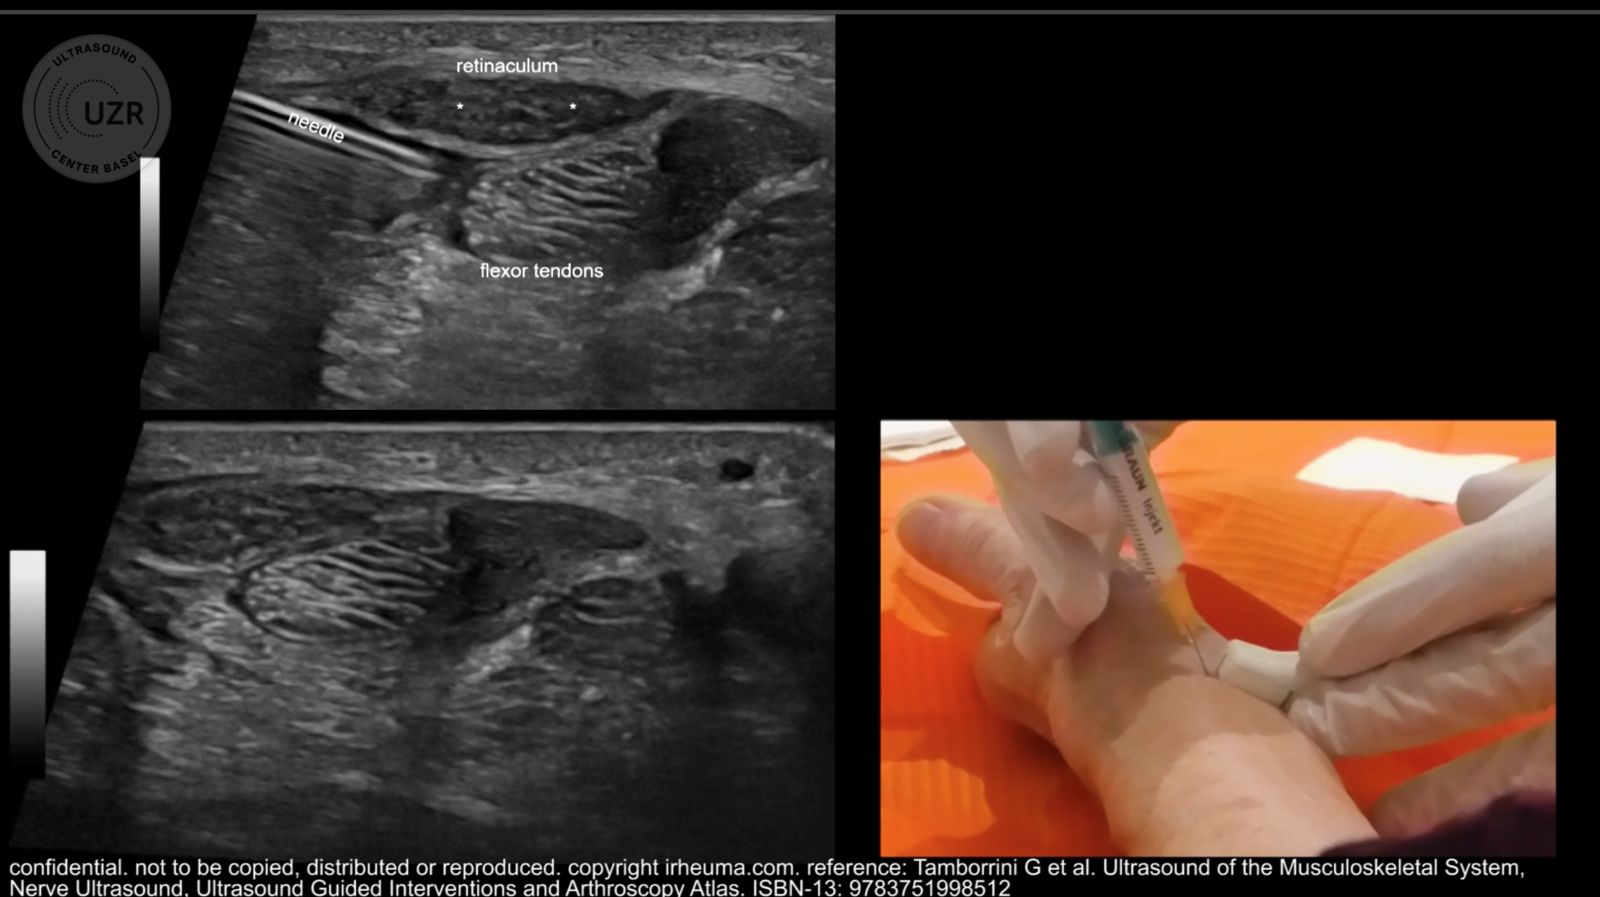

Ultrasound-guided interventions are medical procedures that use real-time ultrasound imaging to visualize internal structures and guide minimally invasive interventions. This technology allows healthcare providers to precisely target specific areas within the body, making it an invaluable tool for both diagnostic and therapeutic purposes.

Using the ultrasound images as a guide, a healthcare provider inserts a needle, catheter, or other instruments through the skin and into the target area with precision.

Throughout the procedure, real-time ultrasound images are continuously monitored to ensure the accurate placement of the instrument or the successful completion of the intervention.